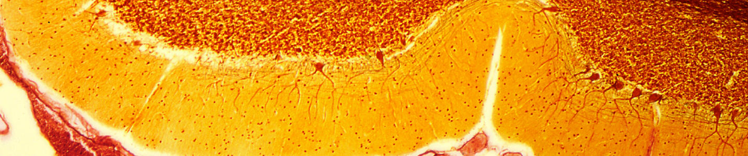

小脑中的浦金野细胞

- 神经元和突触丧失以及新生神经元减少